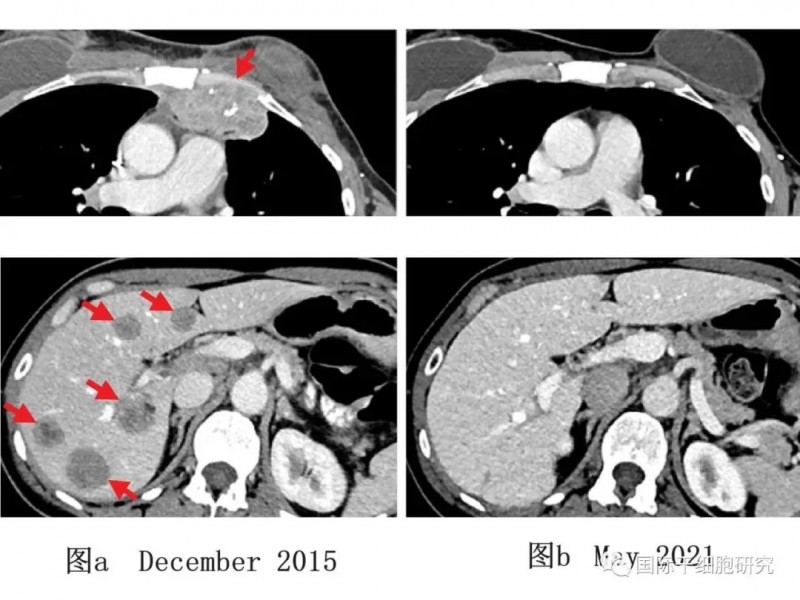

结果显示:50%的患者实现可测量的肿瘤缩小。其中1例2018年研究中记录的患者,至今无癌;另有2例患者肿瘤缩小率分别为52%(治疗6个月后)、69%(治疗10个月后)。上述获肿瘤缩小的患者经TIL治疗后,3.5年及5年内均无新发癌症。

下图展示了一例乳腺癌患者TILs治疗前后影像学变化:下图a(2015年12月,治疗前)显示,患者胸壁(上,左)与肝脏(下,左)均存在转移性病变;下图b(2021年5月,经TILs免疫治疗后)显示,患者肿瘤完全消退,且随访5年未出现新发癌症。